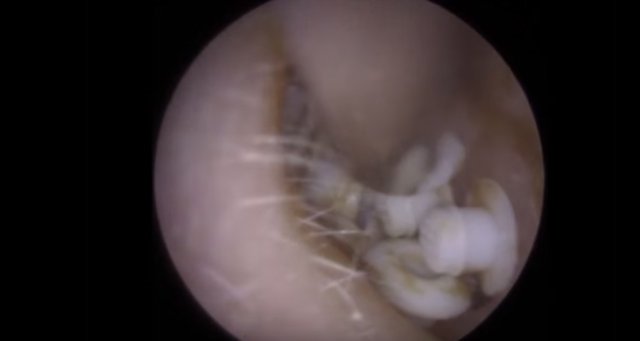

30 yıl boyunca geçmeyen bir baş ağrısı ile yaşayan bir kişi gittiği doktoru şoke etti. Yıllarca baş ağrısı çeken 59 yaşındaki adamın yaşadıkları kan dondurdu. Adamın kafasından öyle bir şey çıktı ki, doktorlar bile şaştı kaldı. İşte şoke eden olayın detayları...